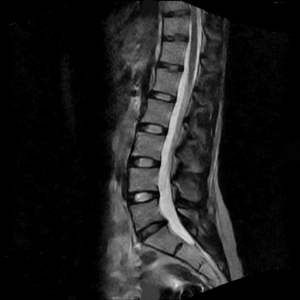

MRI

MRIs, or magnetic resonance imaging, create images of your body using radio waves and a large magnet. MRI may also utilize a contrast material to help identify inflammation, growths or blood supply to certain areas of the body.